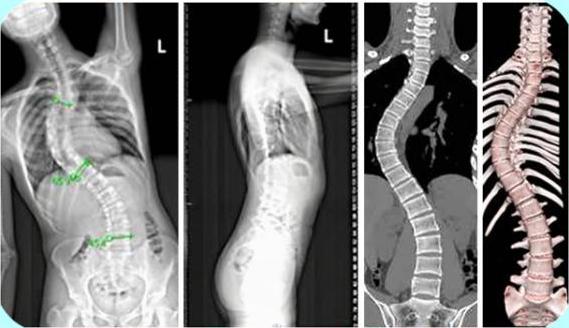

空军军医大学唐都医院骨科廖博教授就曾接诊过一位17岁的脊柱侧弯少年。患者于两年前被诊断出脊柱侧弯未做治疗,两年来,患者一直存在坐姿不正确等情况,且症状呈现进行性加重,患者为进一步诊断、治疗选择唐都医院脊柱外科就诊。

廖博教授接诊后根据患者病史、症状、体征、影像学检查资料等确诊患者存在以胸9和腰2为顶点的两个脊柱侧弯且侧弯角度较大,建议及时行脊柱侧弯畸形矫形术,避免处于发育期的患者侧弯角度将进一步加大。